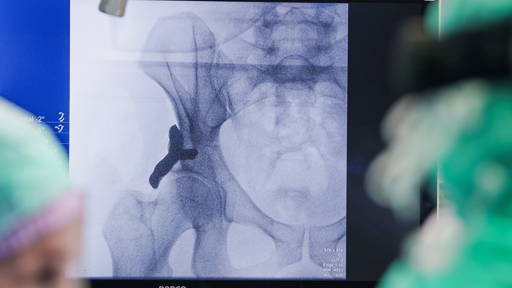

Zuyderland Medisch Centrum is volgens eigen zeggen het eerste ziekenhuis in de Benelux dat een oplosbare, medicijnhoudende stent kan plaatsen bij patiënten met vernauwde bloedvaten in de onderbenen. De stent moet hernieuwde verstoppingen voorkomen en de kans op vervolgoperaties verkleinen. Jaarlijks ondergaan meer dan duizend patiënten in Zuyderland een dotterbehandeling. Na een dotterbehandeling sluiten onderbeenbloedvaten vaak opnieuw, waardoor klachten aanhouden en soms ingrijpende operaties nodig zijn. Met de nieuwe stent hoopt Zuyderland dit probleem te verminderen.

Om de kwaliteit van deze zorg verder te verbeteren, onderzoekt Zuyderland hoe het bloedvat tijdens de behandeling nog preciezer in beeld kan worden gebracht. Met behulp van Optical Coherence Tomography (OCT), een piepkleine camera in het bloedvat, kunnen artsen exact vaststellen hoe groot het bloedvat is en welke behandeling daar het beste bij aansluit. Zo neemt de kans op een blijvend goed resultaat toe.

In het Albert Schweitzer Ziekenhuis (ASZ) wordt dit jaar bij 117 patiënten een biologisch oplosbare stent in een van de kransslagaders rondom het hart geplaatst. Het is een onderdeel van het wetenschappelijk onderzoek Perfect Restore dat is opgezet en wordt uitgevoerd door de cardiologen van ASZ. Stents worden al jarenlang gebruikt om vernauwingen in de kransslagaders te verhelpen.

Twee jaar geleden startten zij met wetenschappelijk onderzoek en inmiddels wordt de stent in de praktijk getest. Daarbij maken zij gebruik van een geavanceerde nieuwe camera, die een zeer gedetailleerd beeld van de ader van binnenuit geeft en het mogelijk maakt de oplosbare stent nog nauwkeuriger te plaatsen. Niet iedereen komt zomaar in aanmerking voor de oplosbare stent. De vernauwing moet geschikt zijn zonder te veel verkalking in de ader en de behandeling mag niet spoedeisend zijn.